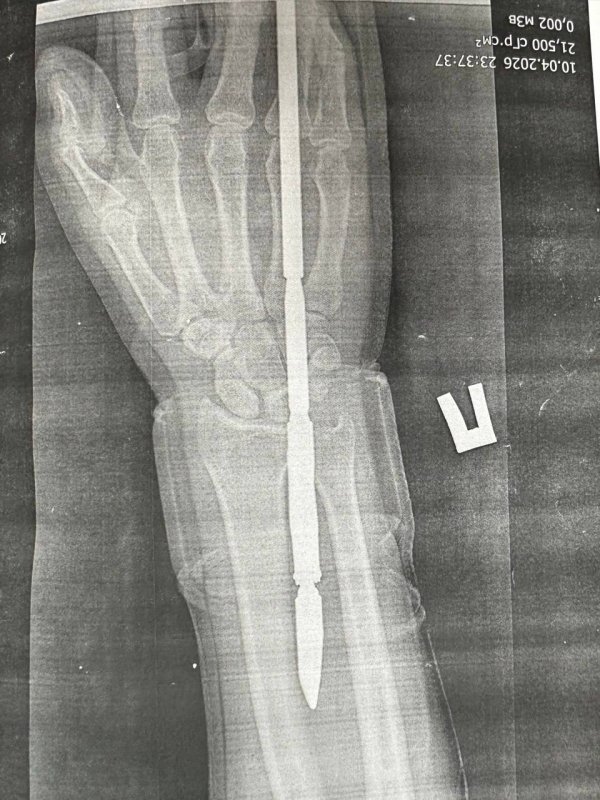

Как рассказали врачи, гарпун с двумя зубцами прошёл между костями — обошлось без перелома. Специалисты аккуратно извлекли инородное тело, обработали рану и оказали всю необходимую помощь.

Фото: ГАУЗ «ГБ» г. Орска